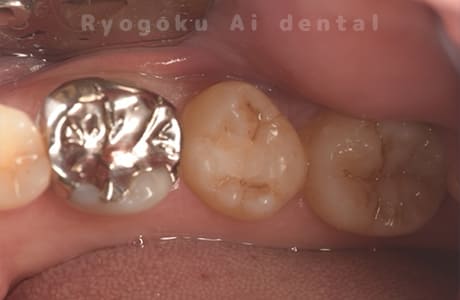

Case11

-

- 原因

- 重度カリエス

- 治療内容

- 自家歯牙移植

- 治療期間

- 約2ヶ月

- 治療費用

- 220,000円

歯が欠けたとのことでご来院された患者様です。虫歯が大きく、保存不可能と判断し、親知らずの移植を行いました。経過良好で、ご本人様も満足されております。

<リスク・副作用>

治療後、痛みや違和感、出血、腫れなどが出る事があります。喫煙者、糖尿病などの方の場合、歯が生着しない場合があります。